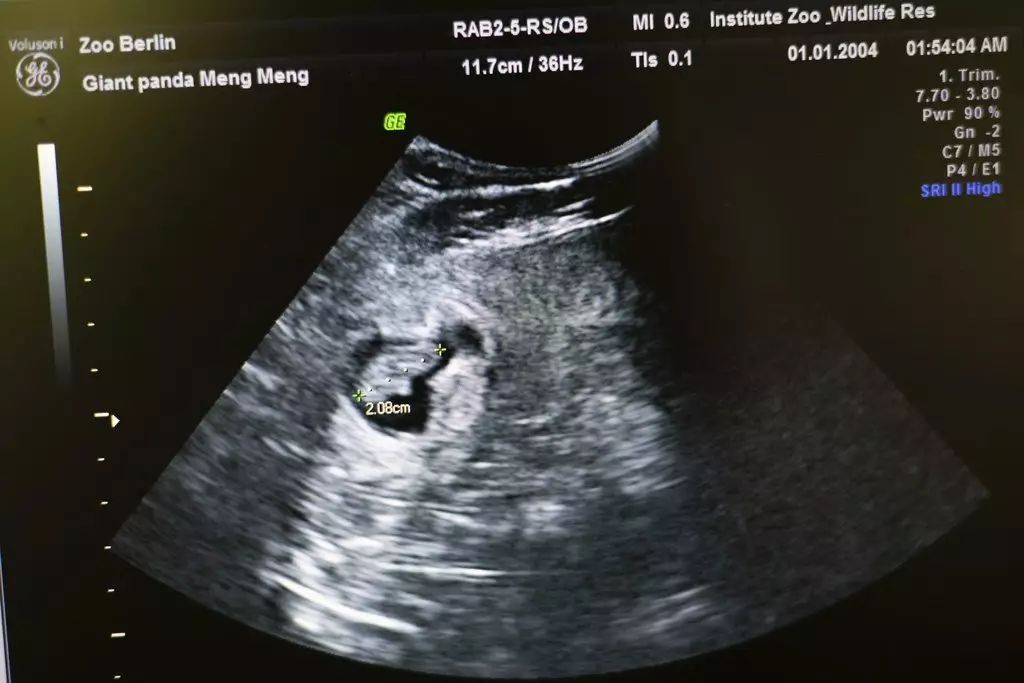

德國柏林動物園宣布,旅居柏林的中國大熊貓「夢夢」繼2019年成功產下一對雙胞胎後,再次確認懷孕,超聲波檢測到兩個胎兒的心跳。

柏林動物園表示,目前兩個大熊貓胎兒身長都約為2.5厘米。園長說,根據胚胎大小推測,牠們會在8月底出生,園方已經為「夢夢」分娩做好充分準備,中國專家也已趕到柏林,為後續工作提供支持。